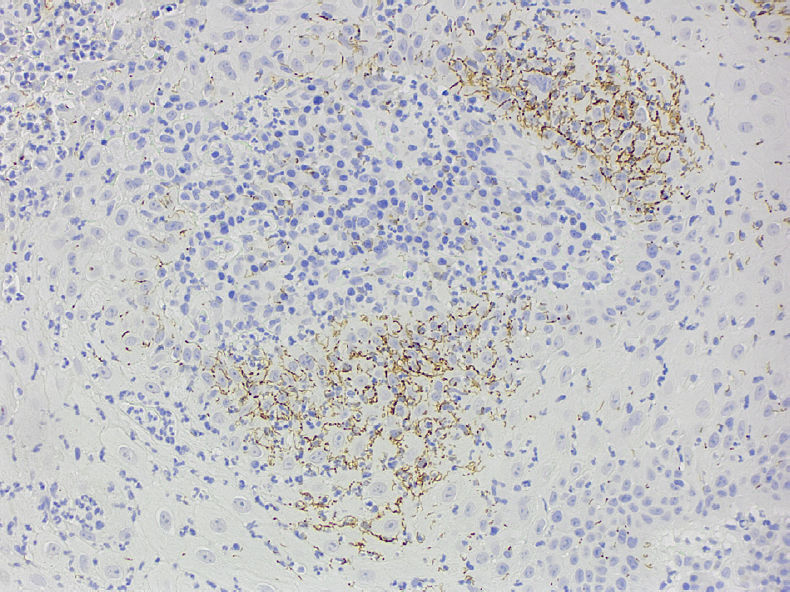

Наличие выраженной воспалительной инфильтрации может указывать на инфекционное заболевание, в частности сифилис. Было выполнено иммуногистохимическое окрашивание на Treponema pallidum, которое выявило большое количество спирохет в эпителии, что позволило установить диагноз сифилиса. С учётом клинических и гистологических данных, а также результатов иммуногистохимического исследования, поражения языка наиболее соответствуют бляшкам при вторичном сифилисе.

Фото 3. Иммуногистохимическое окрашивание выявило большое количество спирохет в пределах эпителия